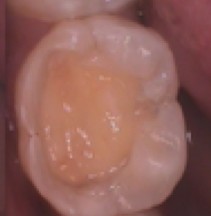

«Я собираюсь показать преимущества работы с использованием глутеральдегида как второго шага во всех total-etch адгезивных техниках—каждый раз, когда вы используете бондинговые системы 4го или 5го поколений.»

Глютеральдегид, популяризированный брендом Gluma (Heraeus Kulzer), стал широко известным компонент дополнительной десенсибилизации, но преимущества глютеральдегида выходят широко за рамки десенсибилизации . Это не только десенсибилизация, но так же дезинфекция, усиление степени пенетрации бондингового агента и так же пролонгированное действие вашего бонда. Gluma используется как десенсибилизирующий агент с 1991 года и это комбинация 5% глютеральдегида и 35% гидроксиэтил метакрилата (HEMA).